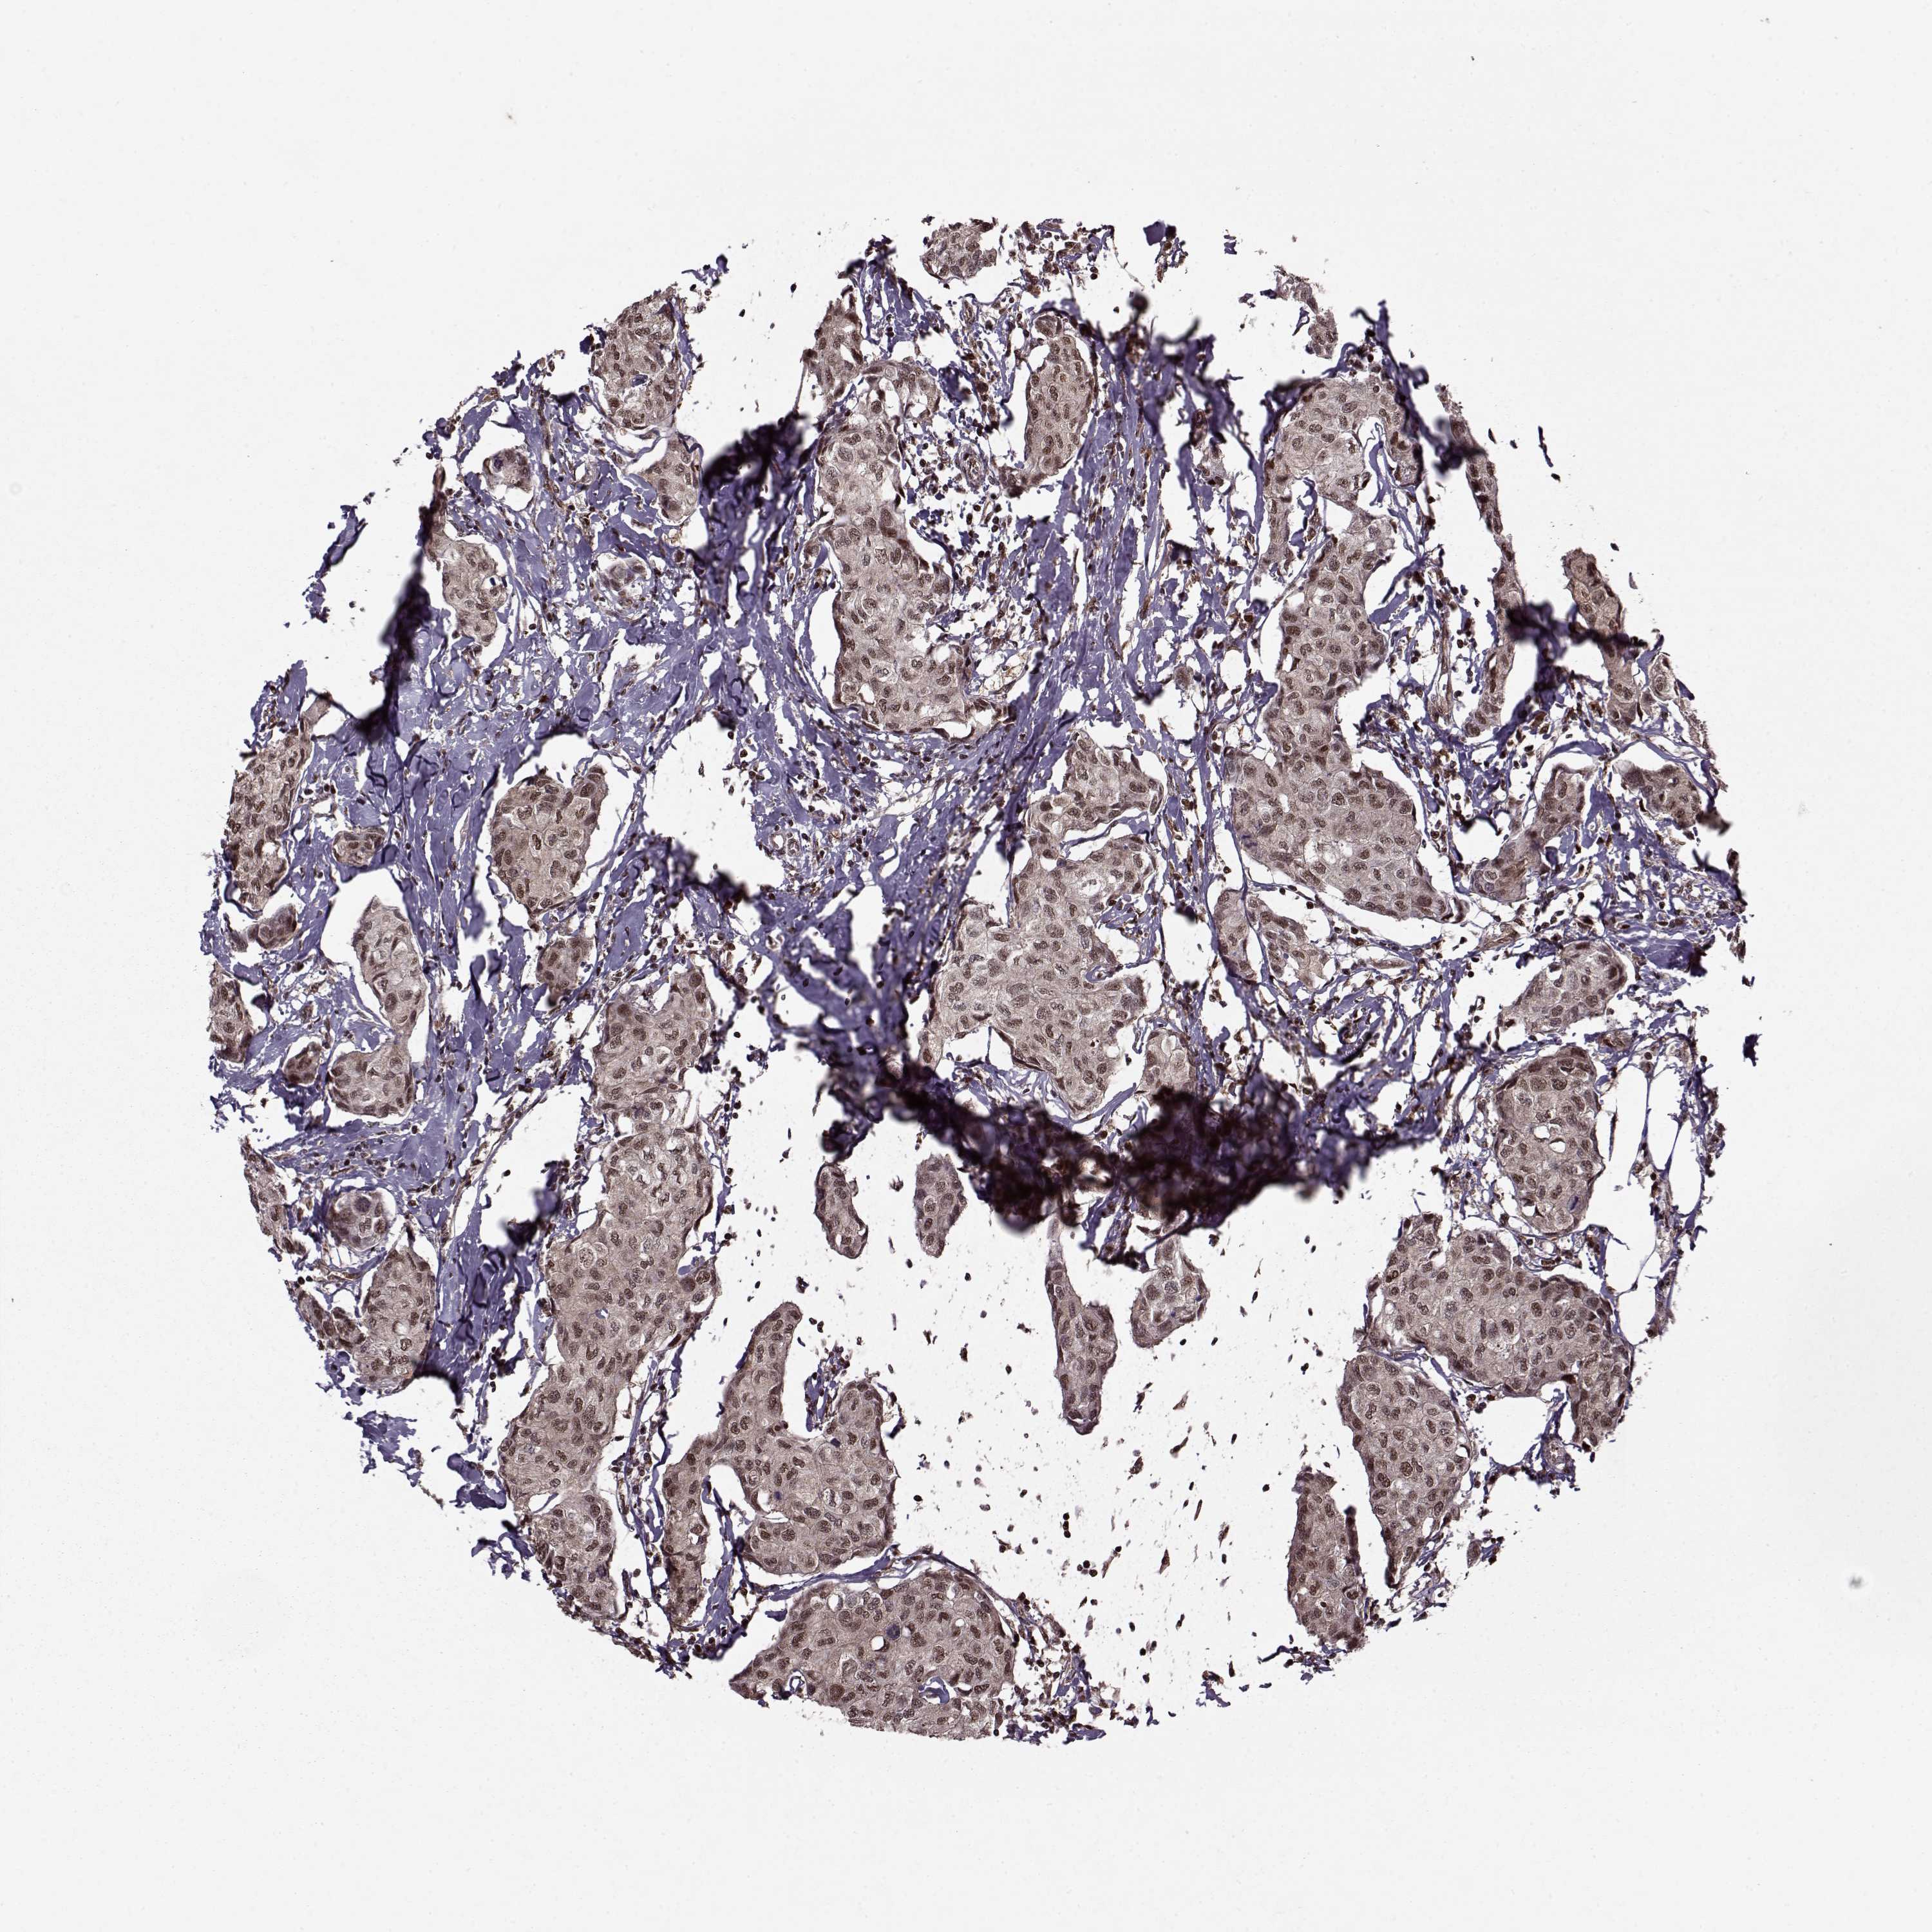

BRCA TCGA BRCA VALIDATION PROTEIN EXPRESSION

ANTIBODIES

AND

VALIDATION